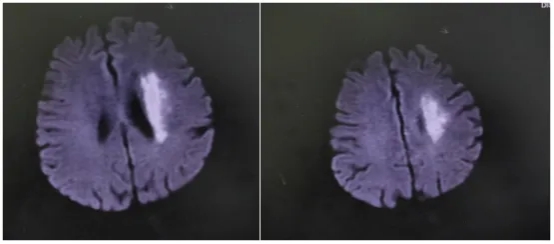

那天,71岁的符阿婆在家突发右侧肢体无力,说话也变得含糊不清。紧急送医后,检查结果令人揪心——左侧大脑中动脉M1段闭塞。

“当时情况非常紧急,”主管医生刘婷回忆道,“造影后发现符阿婆血管闭塞远端血流灌注严重不足,考虑是‘低灌注’导致核心梗死区周围的脑组织(缺血半暗带)也濒临坏死边缘。这意味着,虽然发病时间已较长,但仍有大量脑组织处在‘生死边缘’,若不立即干预,瘫痪将不可逆转。”

“时间就是大脑,虽然超过了常规时间窗,但根据最新的诊疗理念和影像学评估,我们判断患者仍存在可挽救的脑组织。”李威副主任医师解释道,“大脑中动脉全程闭塞,就像一棵树的主干被砍断,远端所有枝叶都将枯萎。我们必须尽快‘接通’主干,恢复血流。”

手术台上,一场与时间的赛跑再次开启。介入团队在DSA(数字减影血管造影)的精确引导下,将微导管、球囊等器械精准送达大脑深处闭塞的血管处。首先用球囊扩张,撑开狭窄闭塞的血管,随后成功植入一枚支架,牢牢“撑住”了病变血管,重建了血流。